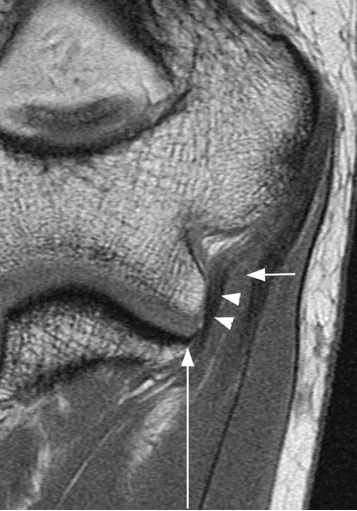

滑膜皱襞

后外侧滑膜皱襞,是关节滑膜增生折叠形成的结构,过度增生或损伤时可能引发关节不适。

(a)33 岁女性受试者的矢状位 T2 加权磁共振成像,以及(b)对应的示意图,清晰显示出后外侧滑膜皱襞的前后径(白色箭头所示)与头尾径(黑色箭头所示)。图中 AM 代表肘肌。

(c)与图 a 相同的磁共振影像,以及(d)对应的示意图,显示出肱骨小头的假性缺损(箭头所示),及其与后外侧滑膜皱襞的密切关联。图中 AM 代表肘肌。